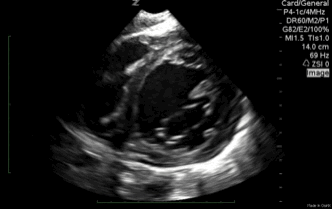

QA of the day. Nice PSS! Global hypokinesis, low EF. Mitral valve view, septum and moderator band. #pocus # foamed # foamus # meded

cardiac – chordae tendonae of mv, low ef, pce, pss, amazing